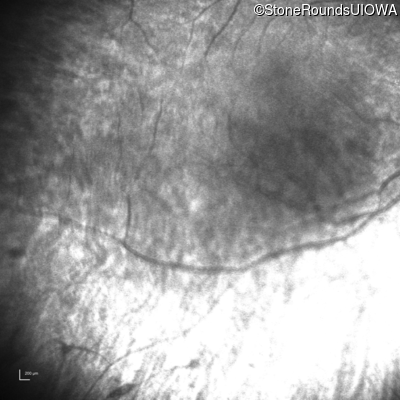

Infrared Fundus Photograph - Right - Light Perception

Exemplar